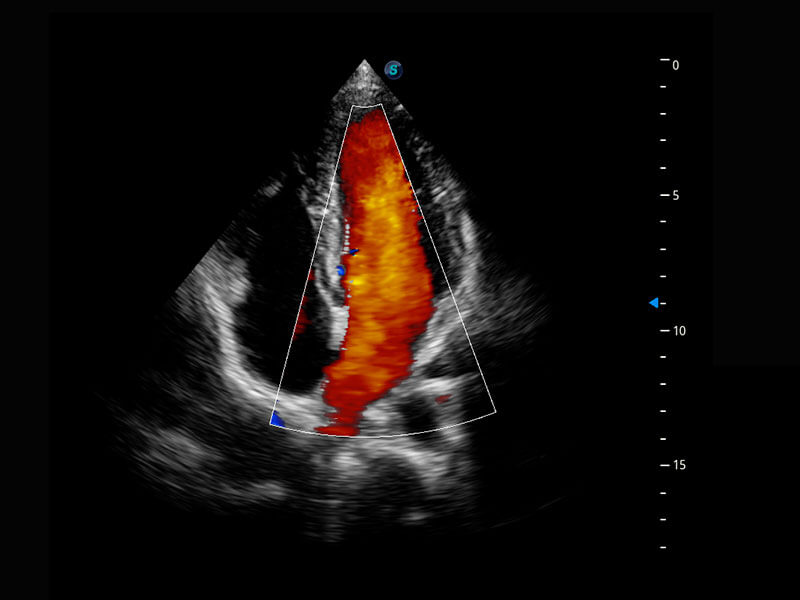

新生儿心脏

P60搭载宽频带线阵探头、宽景成像、弹性成像技术,为您提供乳腺应用方案。P60支持高频相控阵探头、线阵探头、腹部高频探头、腹部微凸探头等,丰富的探头群搭载敏感的彩色血流成像,适用于新生儿多种脏器检测要求,满足新生儿筛查需求。